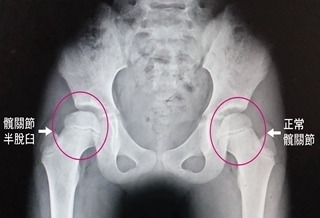

(優活健康網記者林奐妤/綜合報導)80歲的黃女士是高血壓患者,停機車時不穩跌倒,被機車壓到左側髖部,導致疼痛、不良於行,送急診救治後,經身體理學檢查及X光檢查,確診為左側股骨頸骨折。經微創直接前側入路人工半髖關節置換後恢復良好,術後第2天即可持助行器下床走路,並於術後第5天出院,後續追蹤恢復穩定。微創直接前側入路人工髖關節置換 術後傷口更小奇美醫學中心骨科部一般骨科主任黃柏昌說明,髖關節置換手術已經成為治療嚴重髖關節退化或骨折的有效且成熟的治療方法。近年來經微創直接前側入路人工髖關節置換,指利用闊筋膜張肌和縫匠肌的間隙進入髖關節,對入路周圍的肌肉沒有切開損傷。此新式手術方式比例逐年上升,有別以往傳統人工髖關節入路,破壞的組織肌肉少、術後疼痛更輕、術後早期恢復快速。此手術方式,術中失血量、術後需輸血的比例都較傳統手術低,脫臼的機率也較低。直接前側入路病人採平躺姿勢,可以精準直接量測髖關節置換後的兩腳長度,避免長短腿的問題,傷口也較小。術後可以早點行走、進行日常生活功能復健,有效預防長期臥床導致的肺炎、泌尿道感染、褥瘡、下肢靜脈血栓風險及肺栓塞等潛在風險,且能有效減少嗎啡類止痛藥劑用量,並且縮短住院時間。有股外側皮神經損傷、術中周圍骨折風險黃柏昌主任提醒,任何手術都存在風險,直接前側入路手術需注意股外側皮神經損傷、術中人工關節周圍骨折等風險。股外側皮神經損傷表現為暫時性大腿前側麻木,能夠治療恢復。術中人工關節周圍骨折機率約1.7%,好發於股骨大轉子。發生的病人多數不影響術後功能,僅極少數病人會合併脫臼。可採用直接前側入路(全/半)髖關節置換手術的疾病有股骨頭缺血性壞死、60歲以上老年人股骨頸骨折、晚期髖骨關節炎、類風濕性關節炎、僵直性脊椎炎、各種原因導致的髖關節僵直或髖關節脫位或半脫位、腫瘤性疾病等。直接前側入路(全/半)髖關節置換手術,已成為治療髖關節疾病先進有效的技術,造福更多髖關節疾病的病人。